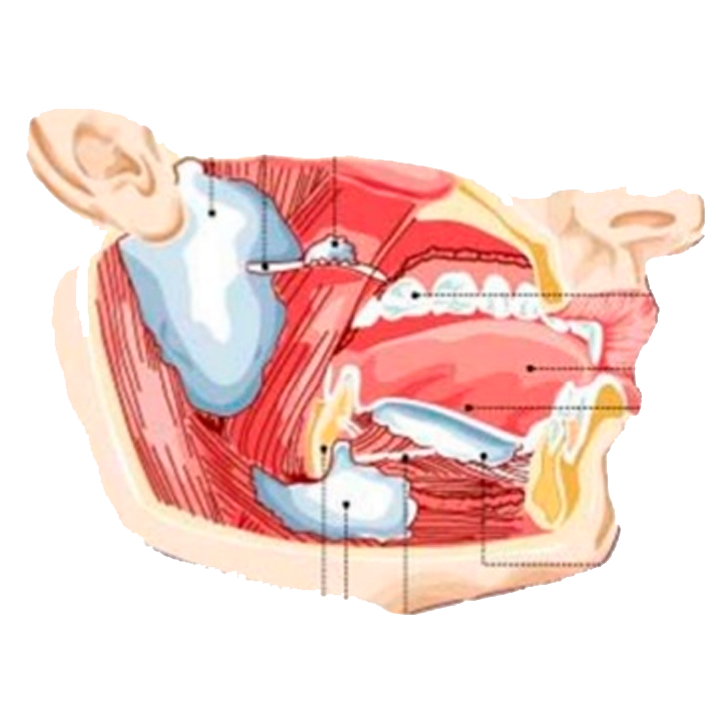

- Ver expedienteCirugía de 3os Molares